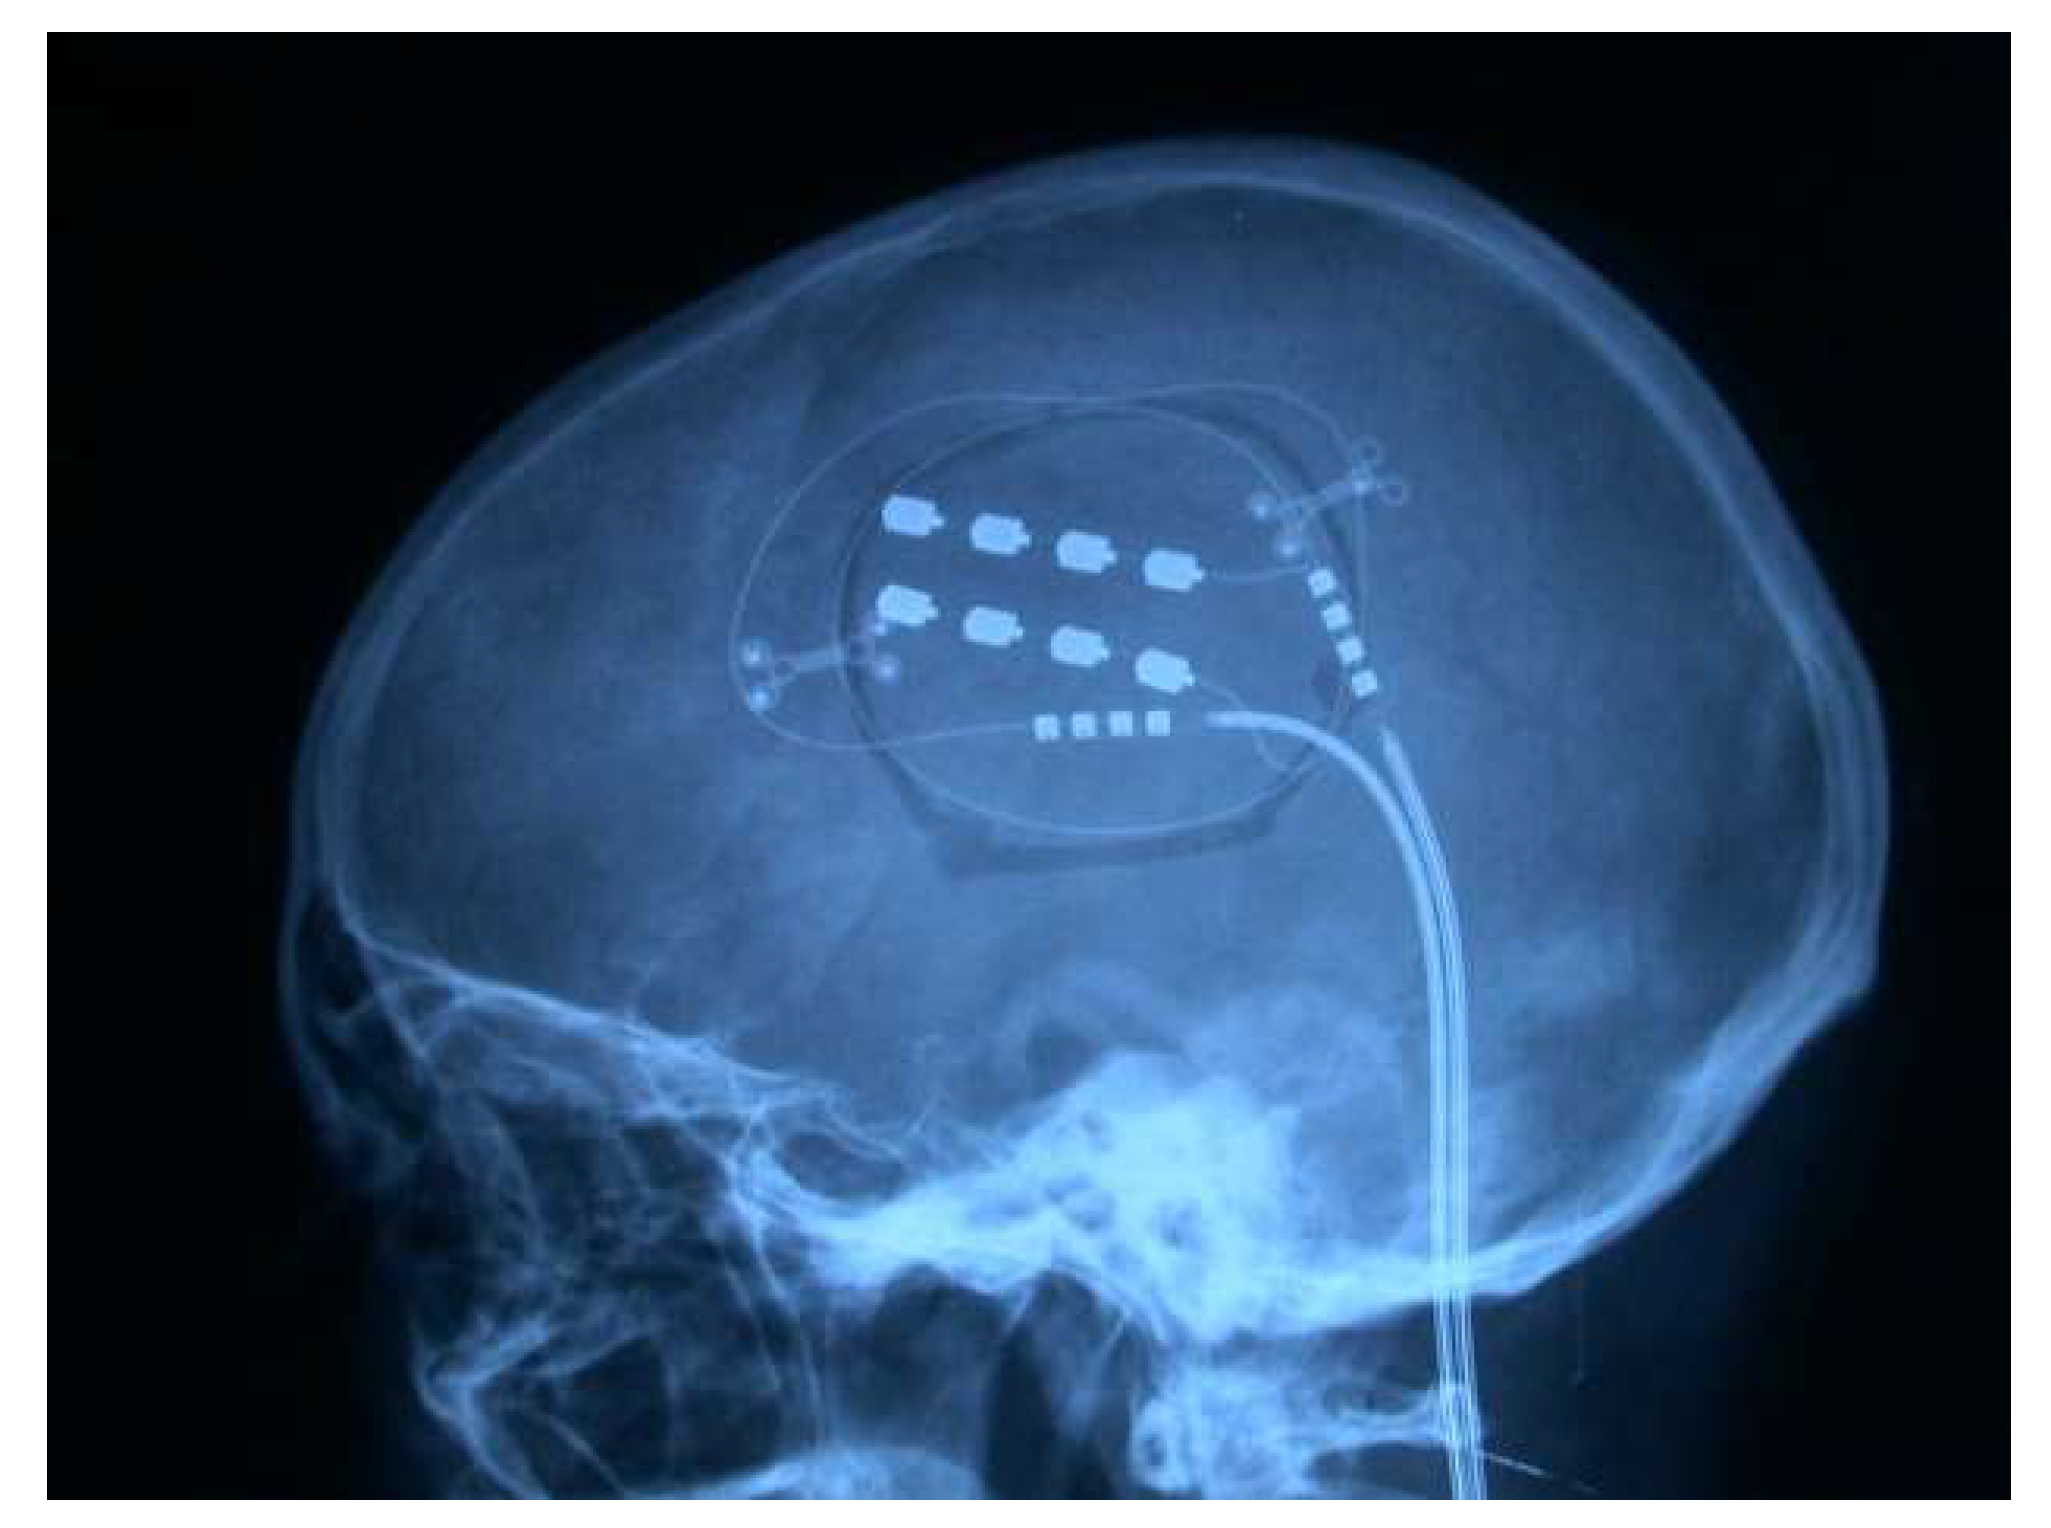

4.4.6. Analgesic Motor Cortex Stimulation (MCS)

Indications and Outcomes

- From the point of view of scientific evidence, the series have better methodological quality than the DBS series [87]. For this procedure, double-blind tests were carried out because patients do not notice anything during stimulation, allowing the treatment to be switched on and off [266,267,268], finding a placebo effect in 35% of patients [269].

- Although it is difficult to summarize all the series, the best responses (up to 70% of patients with more than a 50% reduction in pain intensity) occurred in the following order: facial neuralgia, brachial plexus avulsion, peripheral neuropathies, spinal cord injury, thalamic pain, and phantom limb pain) [266,270,271].

- This technique does not reduce pain to zero for all patients. However, like DBS, it has a very low complication rate, with greater than 60% of patients reporting excellent or good results regarding their pain (reduction of more than 50%, with improved quality of life) [273].

- The mechanism of action involves activating the inhibitory system and modulating the activity of the anterior area of the corpus callosum (pgACC, pregenual anterior cingulate cortex) and the PAG [264].